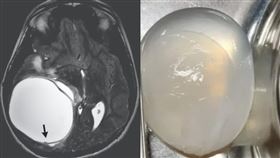

寄生蟲悄悄侵入!14歲男腦長巨大罕見囊腫

印度一名14歲少年在長達一個月的時間出現頭痛、嘔吐症...